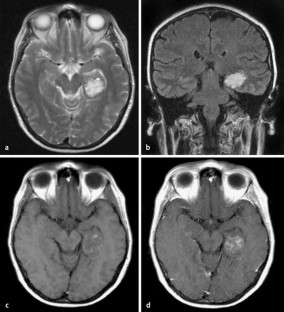

Hemorrhaging occurs when an artery in the brain bursts.

Damage control surgery refers to limited surgical interventions that serve to control haemorrhage and minimize contamination until the patient has sufficient physiological reserve to undergo definitive interventions. The excess blood in the brain causes a pressure buildup, which can. To avoid unsatisfactory results, it is best to choose a surgeon who has completed. Philippines has been growing as hub for medical tourism.